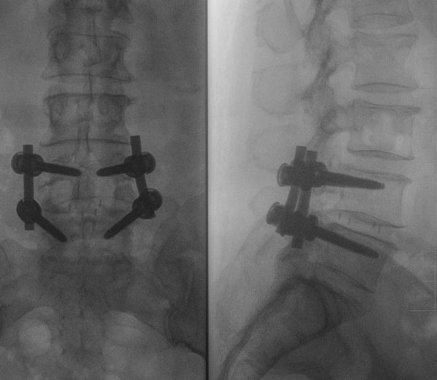

- stabilizacje transpedicularne i implanty międzytrzonowe PLIF Plivios ,

- stabilizacja transpedicularna przy złamaniu kręgosłupa lędźwiowego,

- stabilizacja kręgosłupa z wykorzystaniem śrub kaniulowanych,